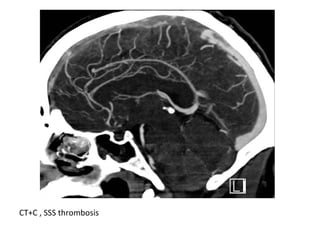

CT+C , SSS thrombosis

CT+C : Empty delta sign due to thrombosis of the SSS